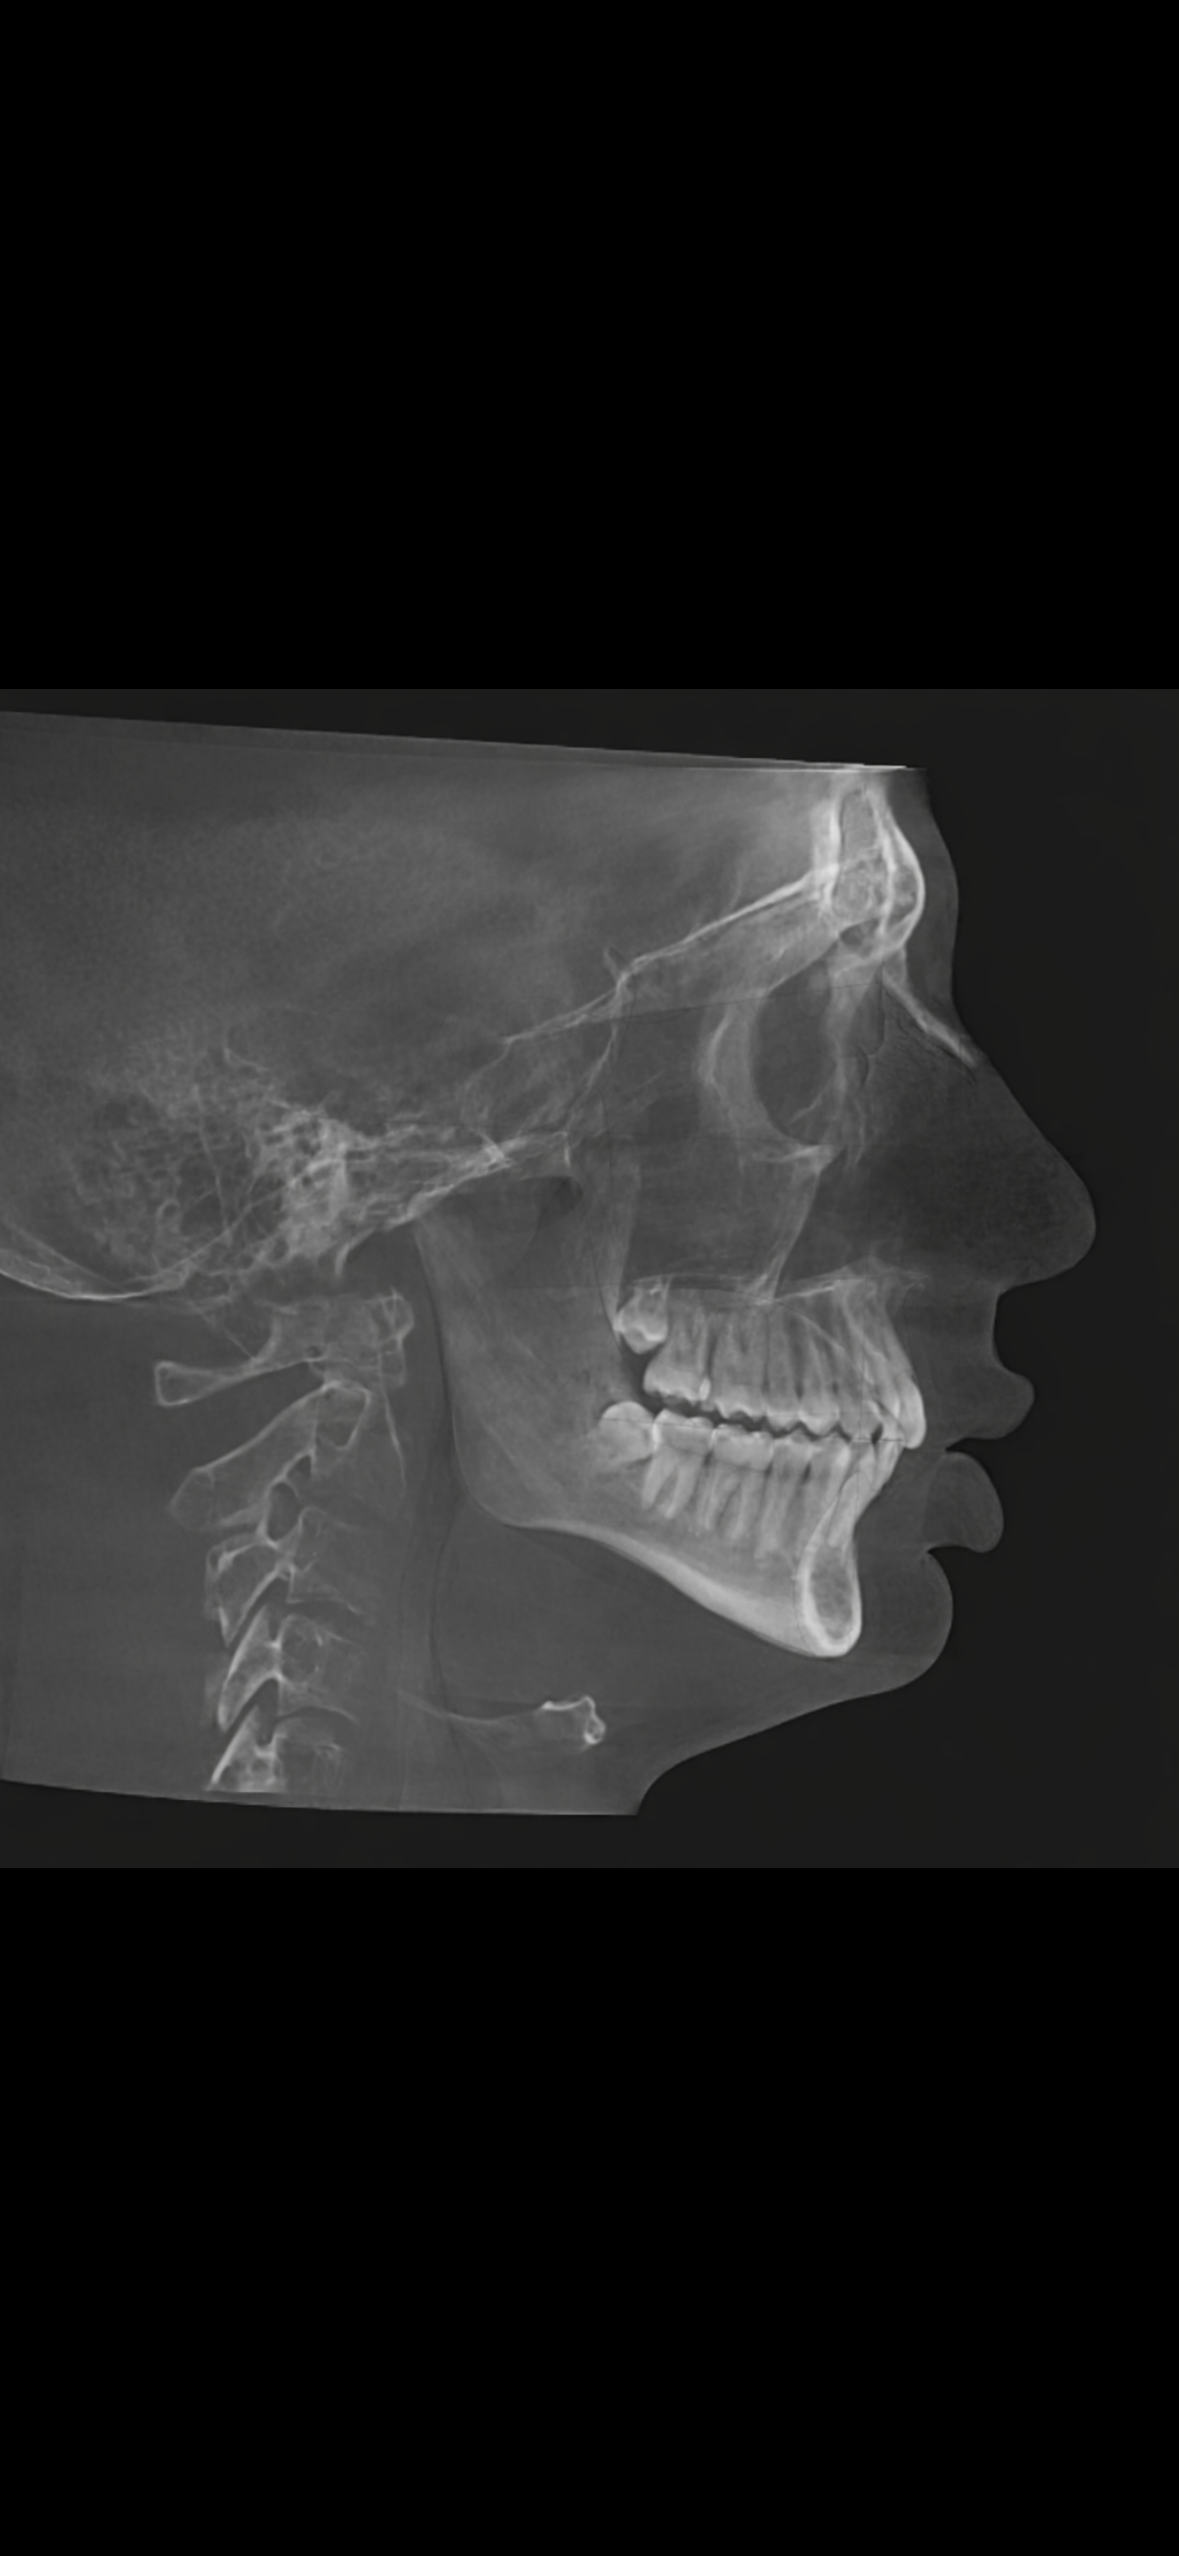

Look at photos at the bottom, 6'0 so I wouldn't consider ll, 20yo. Feel as if my 2 largest points are jaw/chin recession and my lack of infraorbital support. Ive done infra orbital prf a few times for the coloring. For my lower third my only option is trimax. Jutting is easy, but I am not going to rely on it for the rest of my life lmao. Have seen mixed reviews on tear trough implants so skeptical on that. (No sure why the photos uploaded so lq)